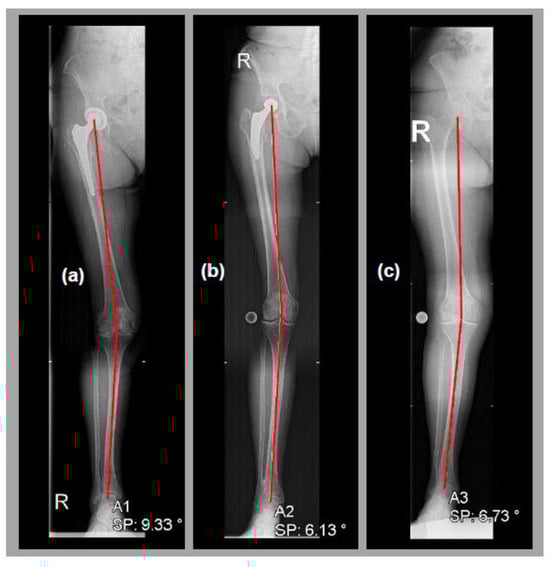

- Sheehy, L.; Felson, D.; Zhang, Y.; Niu, J.; Lam, Y.-M.; Segal, N.; Lynch, J.; Cooke, T. Does measurement of the anatomic axis consistently predict hip-knee-ankle angle (HKA) for knee alignment studies in osteoarthritis? Analysis of long limb radiographs from the multicenter osteoarthritis (MOST) study. Osteoarthr. Cartil. 2011, 19, 58–64. [Google Scholar] [CrossRef]